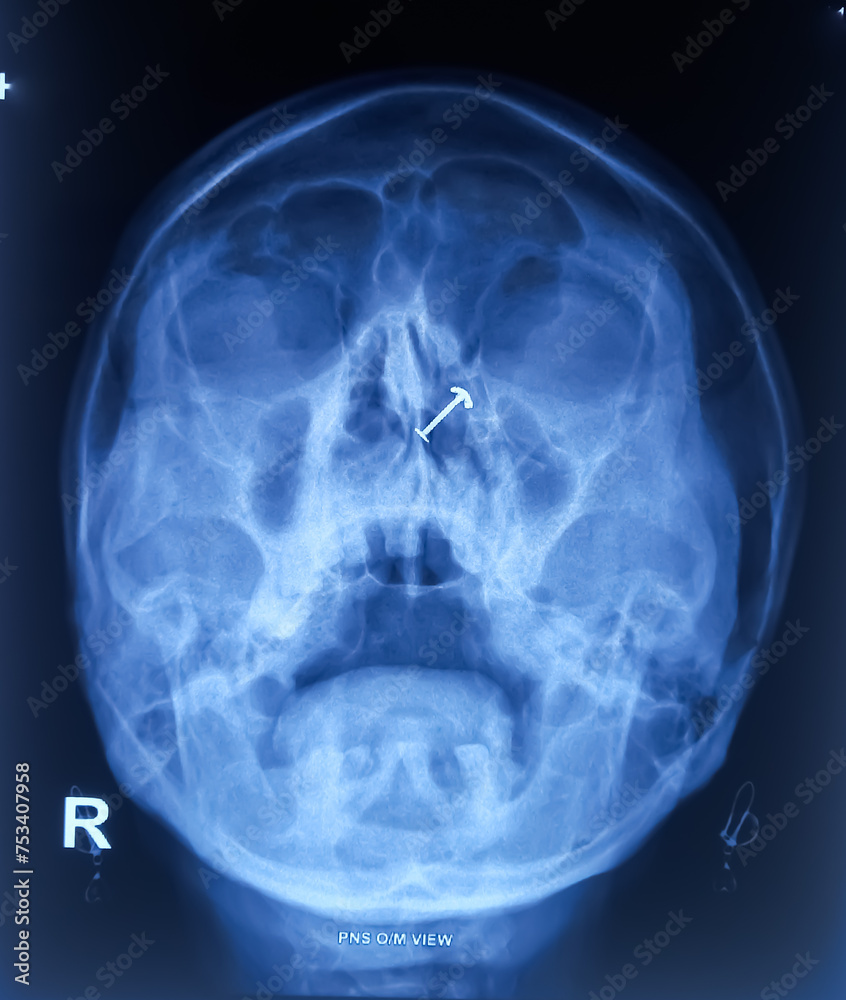

From stock.adobe.com

PNS Xray OM view film, bilateral maxillary sinusitis with What Is Pns X Ray All are normally paired, except. Patient position, technical parameters, and criteria for success for lateral and pa views. Paranasal sinuses enable the circulation of the air breathed in and out of the respiratory system(2). The nasal cavity is a system of air channels that connect the nose with the back of the throat. The paranasal sinuses are derived from ectoderm. What Is Pns X Ray.